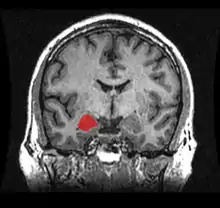

The amygdala (/əˈmɪɡdələ/; PL: amygdalae /əˈmɪɡdəli, -laɪ/ or amygdalas; also corpus amygdaloideum; Latin from Greek, ἀμυγδαλή, amygdalē, 'almond', 'tonsil'[1]) is one of two almond-shaped clusters of nuclei located deep and medially within the temporal lobes of the brain's cerebrum in complex vertebrates, including humans.[2] Shown to perform a primary role in the processing of memory, decision making, and emotional responses (including fear, anxiety, and aggression), the amygdalae are considered part of the limbic system.[3] The term "amygdala" was first introduced by Karl Friedrich Burdach in 1822.[4]

Frontal and side view of amygdala

Amygdala along with other subcortical regions, in glass brain.

Dorsal view of the amygdalae in an average human brain

Frontal view of the amygdalae in an average human brain

Left lateral view of the amygdala in an average human brain

Amygdala highlighted in green on coronal T1 MRI images

Amygdala highlighted in green on sagittal T1 MRI images

Amygdala highlighted in green on transversal T1 MRI images